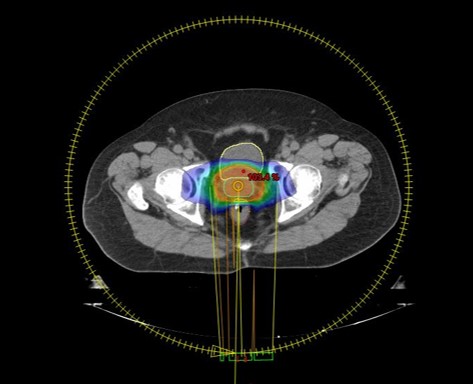

撮影した画像をもとに、放射線治療医・医学物理士・放射線技師が協力して治療計画を作成します。PET-CTやMRIなどの画像を撮影した場合には、それらの画像も活用しながら治療計画を行います。治療計画完成後は、複数の測定器を使って実際に計画通り正確に放射線が照射されているかを慎重に確認しています。

前立腺VMAT